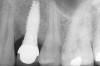

Figure 11  Radiograph demonstrating a quantity of excess cement on the mesial aspect of an implant crown and abutment.

Figure 11